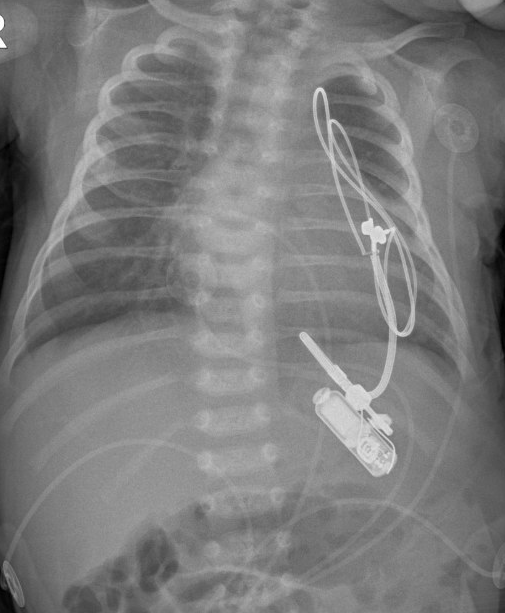

Instead, Tan turned to a pacemaker called Micra, made by the biotechnology company Medtronic. That pacemaker is about the size of a vitamin and weighs as much as a penny, Tan explained, but it was still too large for him. A pacemaker that is too large can lead to "more complications" in patients, Kumar said. It can move around the body, or the thin wires connecting it to the heart can break.

Tan and other members of the pediatric heart team filed for emergency approval to use an adapted version of the device that was suitable for babies. It's the smallest pacemaker in the world. Only about 50 such devices have ever been implanted in the United States. Kumar said the adapted version is inserted and placed over the heart with just one small surgical incision during a 75-minute procedure.

The day he was born, Mikey was approved for the adapted pacemaker. On December 17, he was taken into surgery.